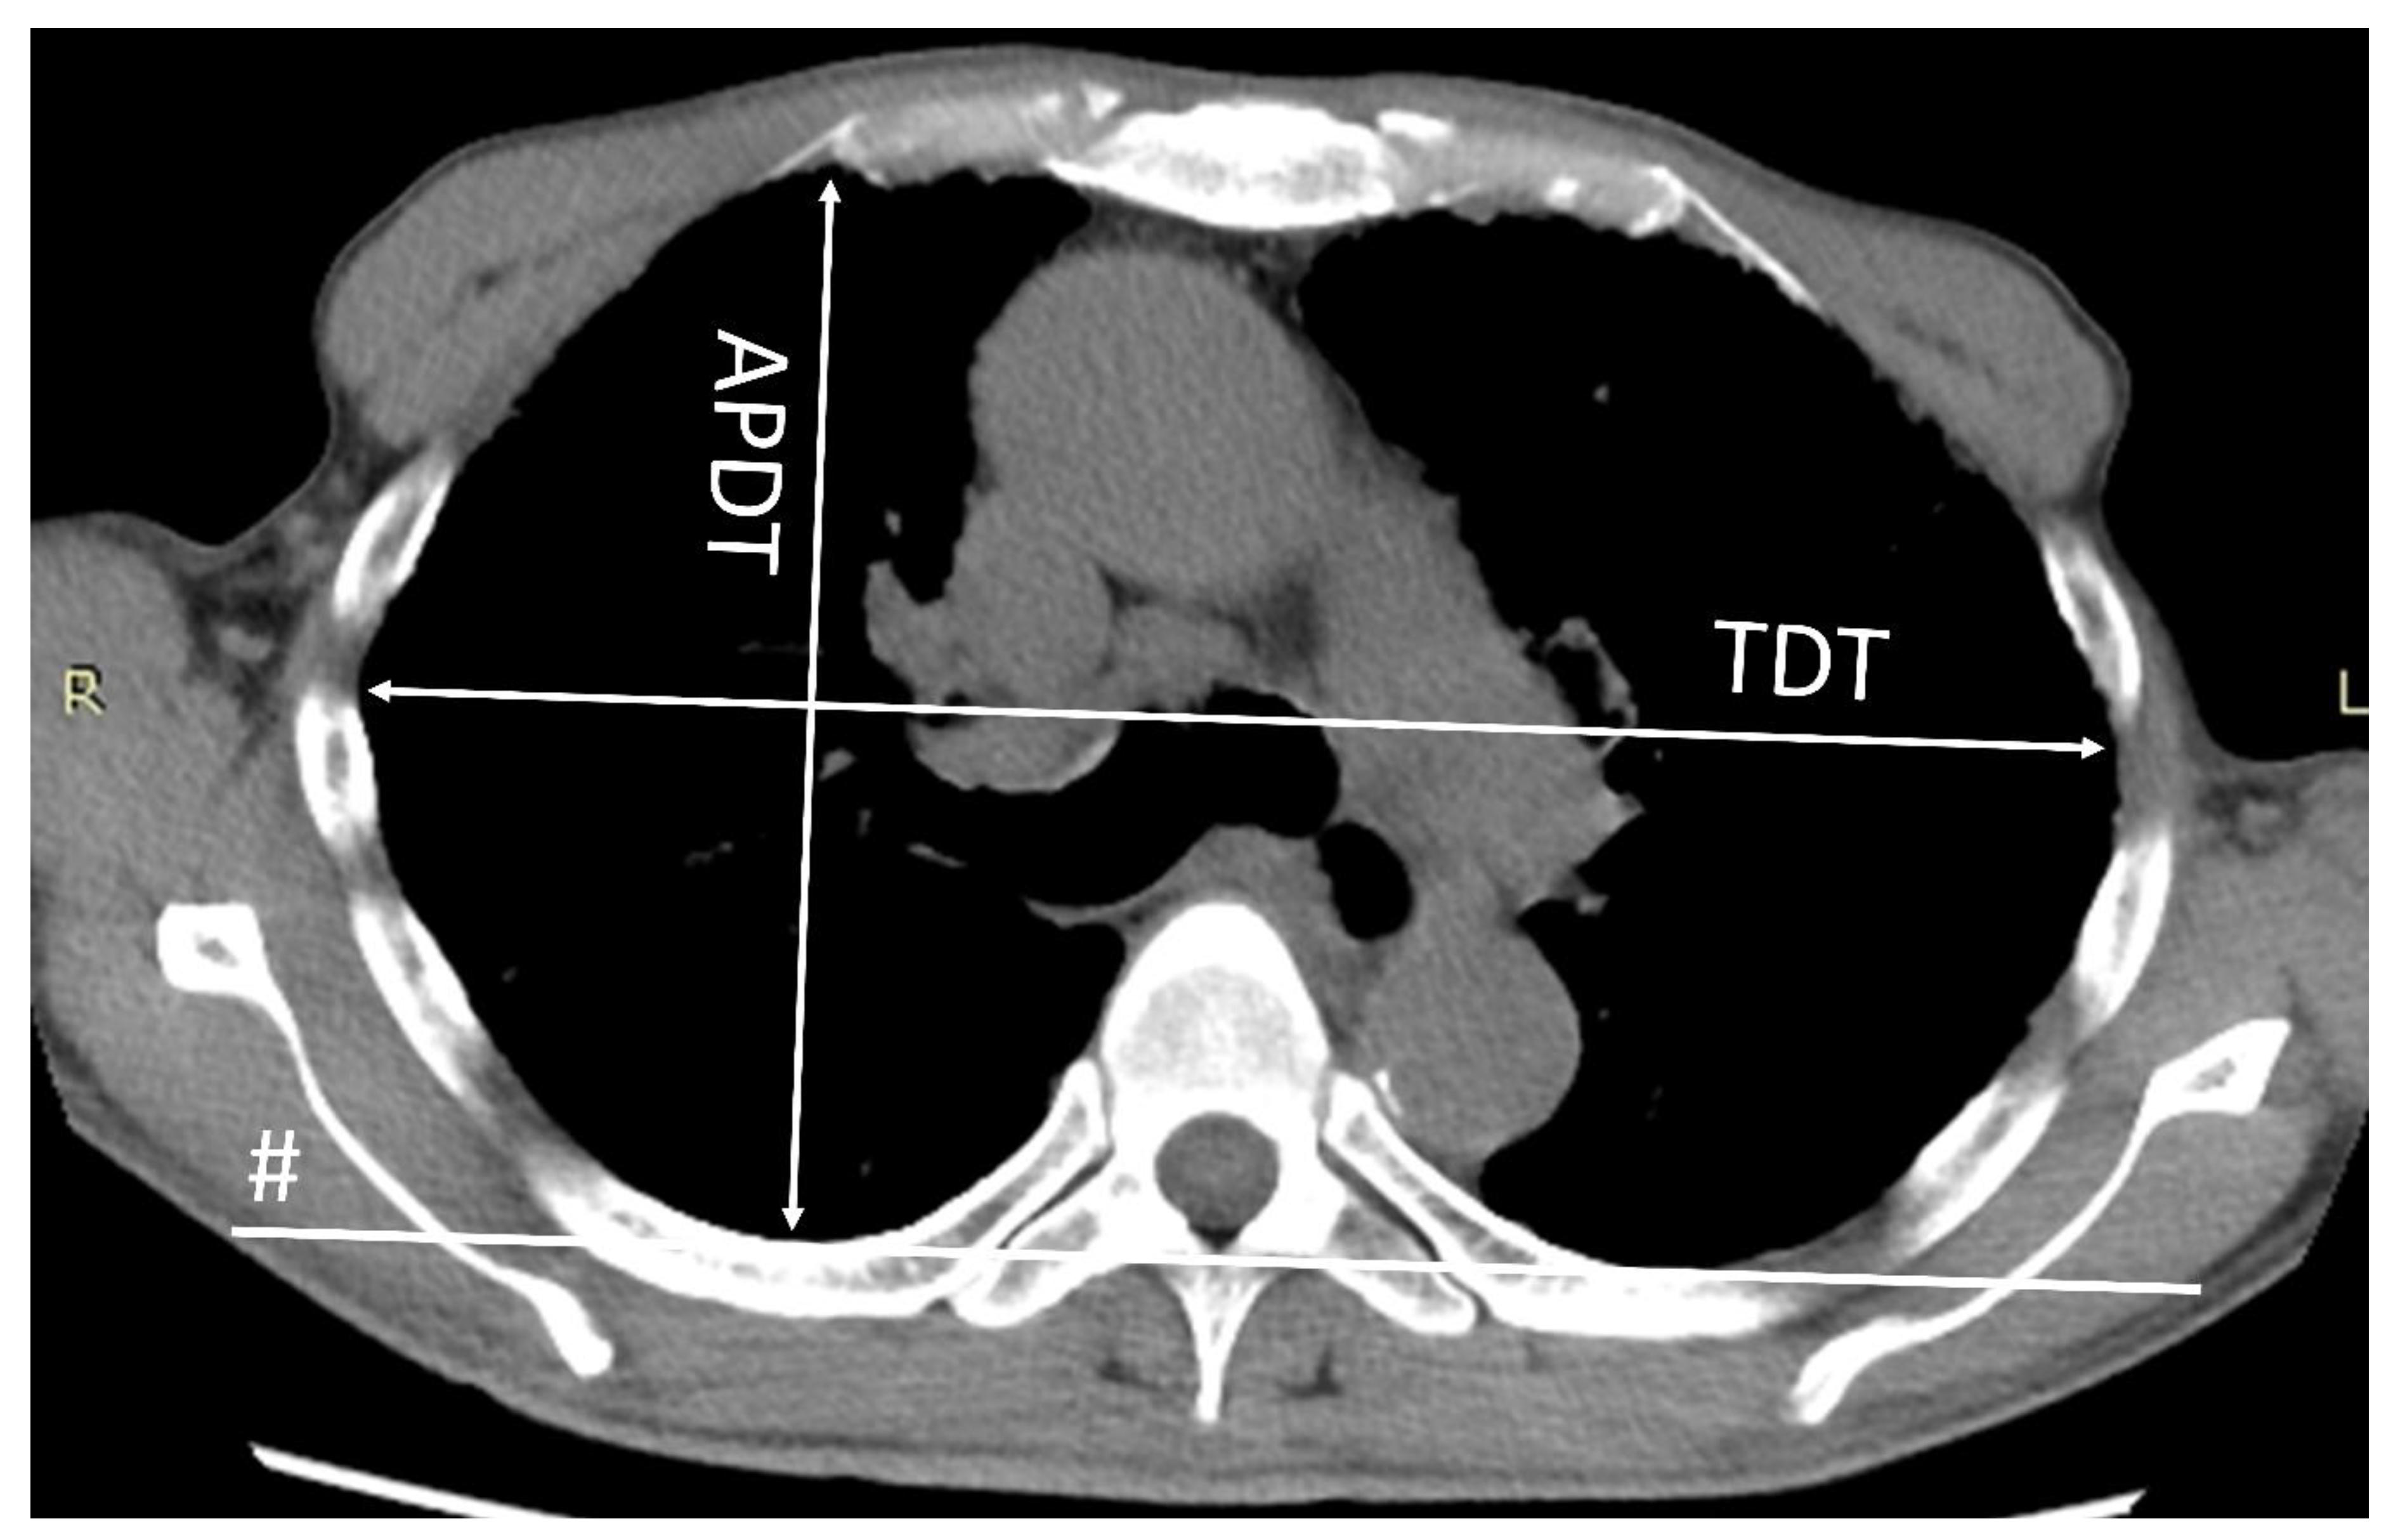

2.3. The Flat Chest Index

The flat chest index was defined as the ratio of the anteroposterior diameter to the transverse diameter of the thoracic cage at the level of the sixth thoracic vertebra on CT, as described previously (Figure 1) [15]. The flat chest index was calculated using the CT scan obtained at the time of the diagnosis. The correlation between the flat chest index and RV/TLC %pred. in IPPFE patients was then analyzed.

Figure 1.

The transverse diameter of the thoracic cage (TDT) was determined as the longest transverse diameter of the thoracic cage measured parallel to a line (#) that runs along the rearmost points of the bilateral 6th ribs in the horizontal section of the CT scan. The anteroposterior diameter of the thoracic cage (APDT) was determined as the longest distance of the anteroposterior dimension of the thoracic cage measured perpendicular to the line along the rearmost points of the sixth thoracic vertebra (line #).